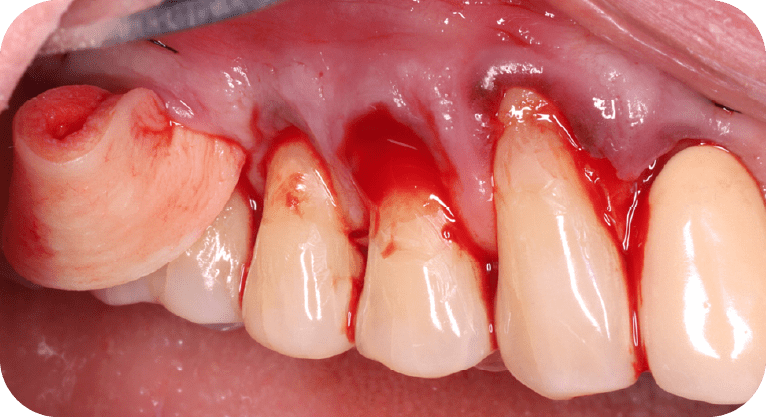

Paciente masculino, “65” años

Tratamiento: Cirugía de encías

El paciente presentaba sensibilidad dental causada por la exposición de los cuellos dentales, por lo que se realizó una cirugía de recubrimiento radicular con injerto gingival y reposicionamiento de encía, logrando

proteger las raíces expuestas, reducir la hipersensibilidad y mejorar tanto la función como la estética periodontal, con resultados satisfactorios para el paciente.